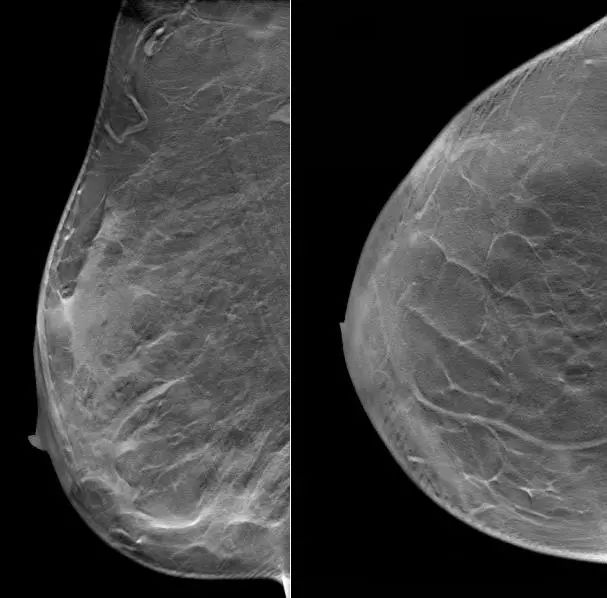

2021.6.28乳腺超声示:右乳外上象限实性肿块,考虑乳腺癌(BI-RADS-5类)。

右乳10点方向腺体层探及一实质低回声肿块,大小约35.1×22.6mm,内部回声不均匀,其内可探及多个点状强回声,边界不清,形态不规则,周边可见毛刺征,CDFI、CDE示其内血供丰富。右侧腋窝探及多个实质低回声结节,大者约10.2×5.2mm,皮质稍增宽,CDFI、CDE示其内血供不丰富。

图1. 乳腺超声